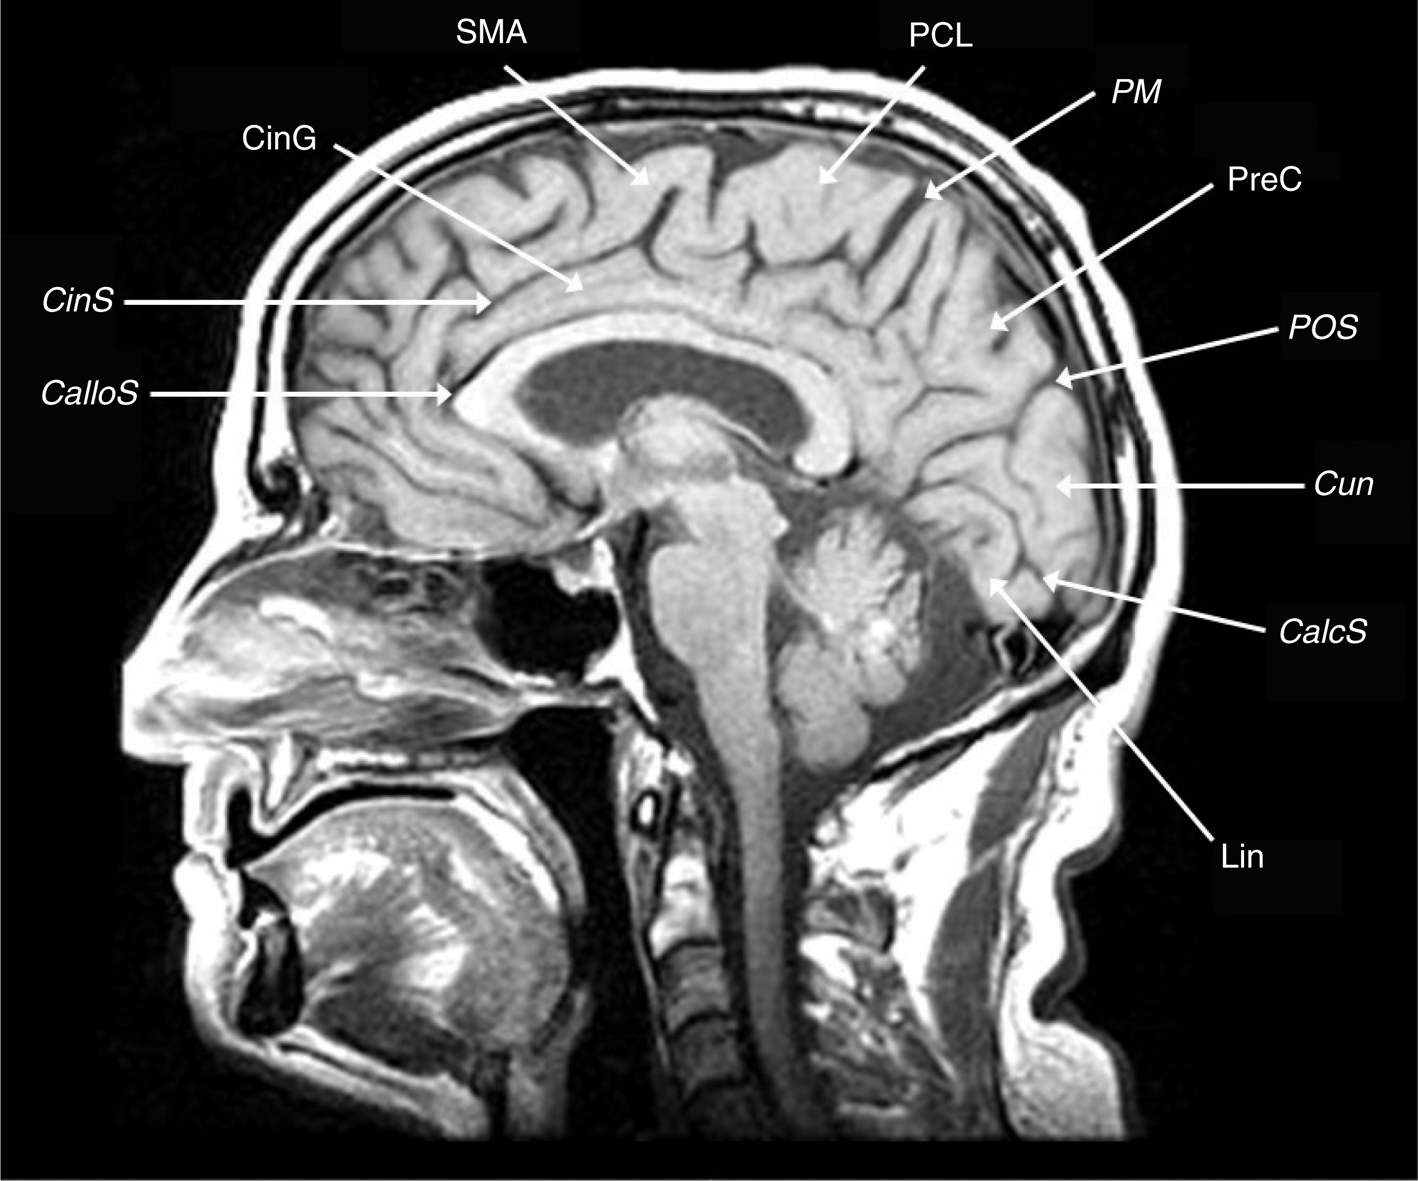

The frontal lobe contains three gyri (superior, middle, inferior) separated by the superior and inferior frontal sulci. The superior frontal gyrus is appreciated on both axial and sagittal images (Figure 1). The middle frontal gyrus (MFG) extends posteriorly and fuses with the vertically oriented precentral gyrus. The precentral sulcus starts at midline and extends anteriorly and laterally in an oblique direction. The next key finding is the merging of the inferior frontal sulcus with the inferior ramus of the precentral sulcus, forming a “T” shape (4, 5). More posteriorly, the central sulcus is identified over the convexity on axial or sagittal images. It is oriented obliquely from posterior to anterior and does not extend all the way into the Sylvian fissure. Inferiorly, the precentral gyrus and postcentral gyrus merge under the central sulcus through a “U”-shaped gyrus (the subcentral gyrus). The post-central gyrus is characteristically narrower than the precentral gyrus (4, 5). Posteriorly, the Sylvian fissure is capped by the SMG, which is the anterior most portion of the inferior parietal lobule. Inferiorly, within the temporal lobe, coursing in parallel with the Sylvian fissure, is the superior temporal sulcus, which is capped posteriorly by the angular gyrus, the posterior limit of the inferior parietal lobule. The angular gyrus (Brodmann’s area 39) and posterior aspect of the superior temporal gyrus (STG) (Brodmann’s area 22) represent the primary receptive speech area (Wernicke’s area). The SMG (Brodmann’s area 40) contains fibers from the arcuate fasciculus that connect Wernicke’s and Broca’s areas (4, 5). The cingulate sulcus separates the cingulate gyrus from the medial aspect of the superior frontal gyrus. If followed posteriorly, the cingulate sulcus angles superiorly to form the pars marginalis, marking the posterior aspect of the paracentral lobule. The paracentral lobule houses the central sulcus, Broadman Areas 3,1,2 and 4,6. On axial images, the pars marginalis may be appreciated as a “bracket” (pars bracket) extending symmetrically from midline left and right. Anterior to this are the primary motor cortex and the postcentral sulcus. Areas 3,1,2 relate to the primary sensory cortex, and areas 4,6 include primary motor and supplemental motor areas (4, 5) (Figures 1 and 2).

Fig 2

Figure 2 Midline sagittal T1-weighted MRI scan showing the callosal sulcus (CalloS); cingulate sulcus (CinS); cingulate gyrus (CinG); supplementary motor area (SMA); paracentral lobule (PCL); pars marginalis (PM); precuneus (PreC); parietal-occipital sulcus (POS); cuneus (Cun), calcarine sulcus (CalcS), lingula (Lin).